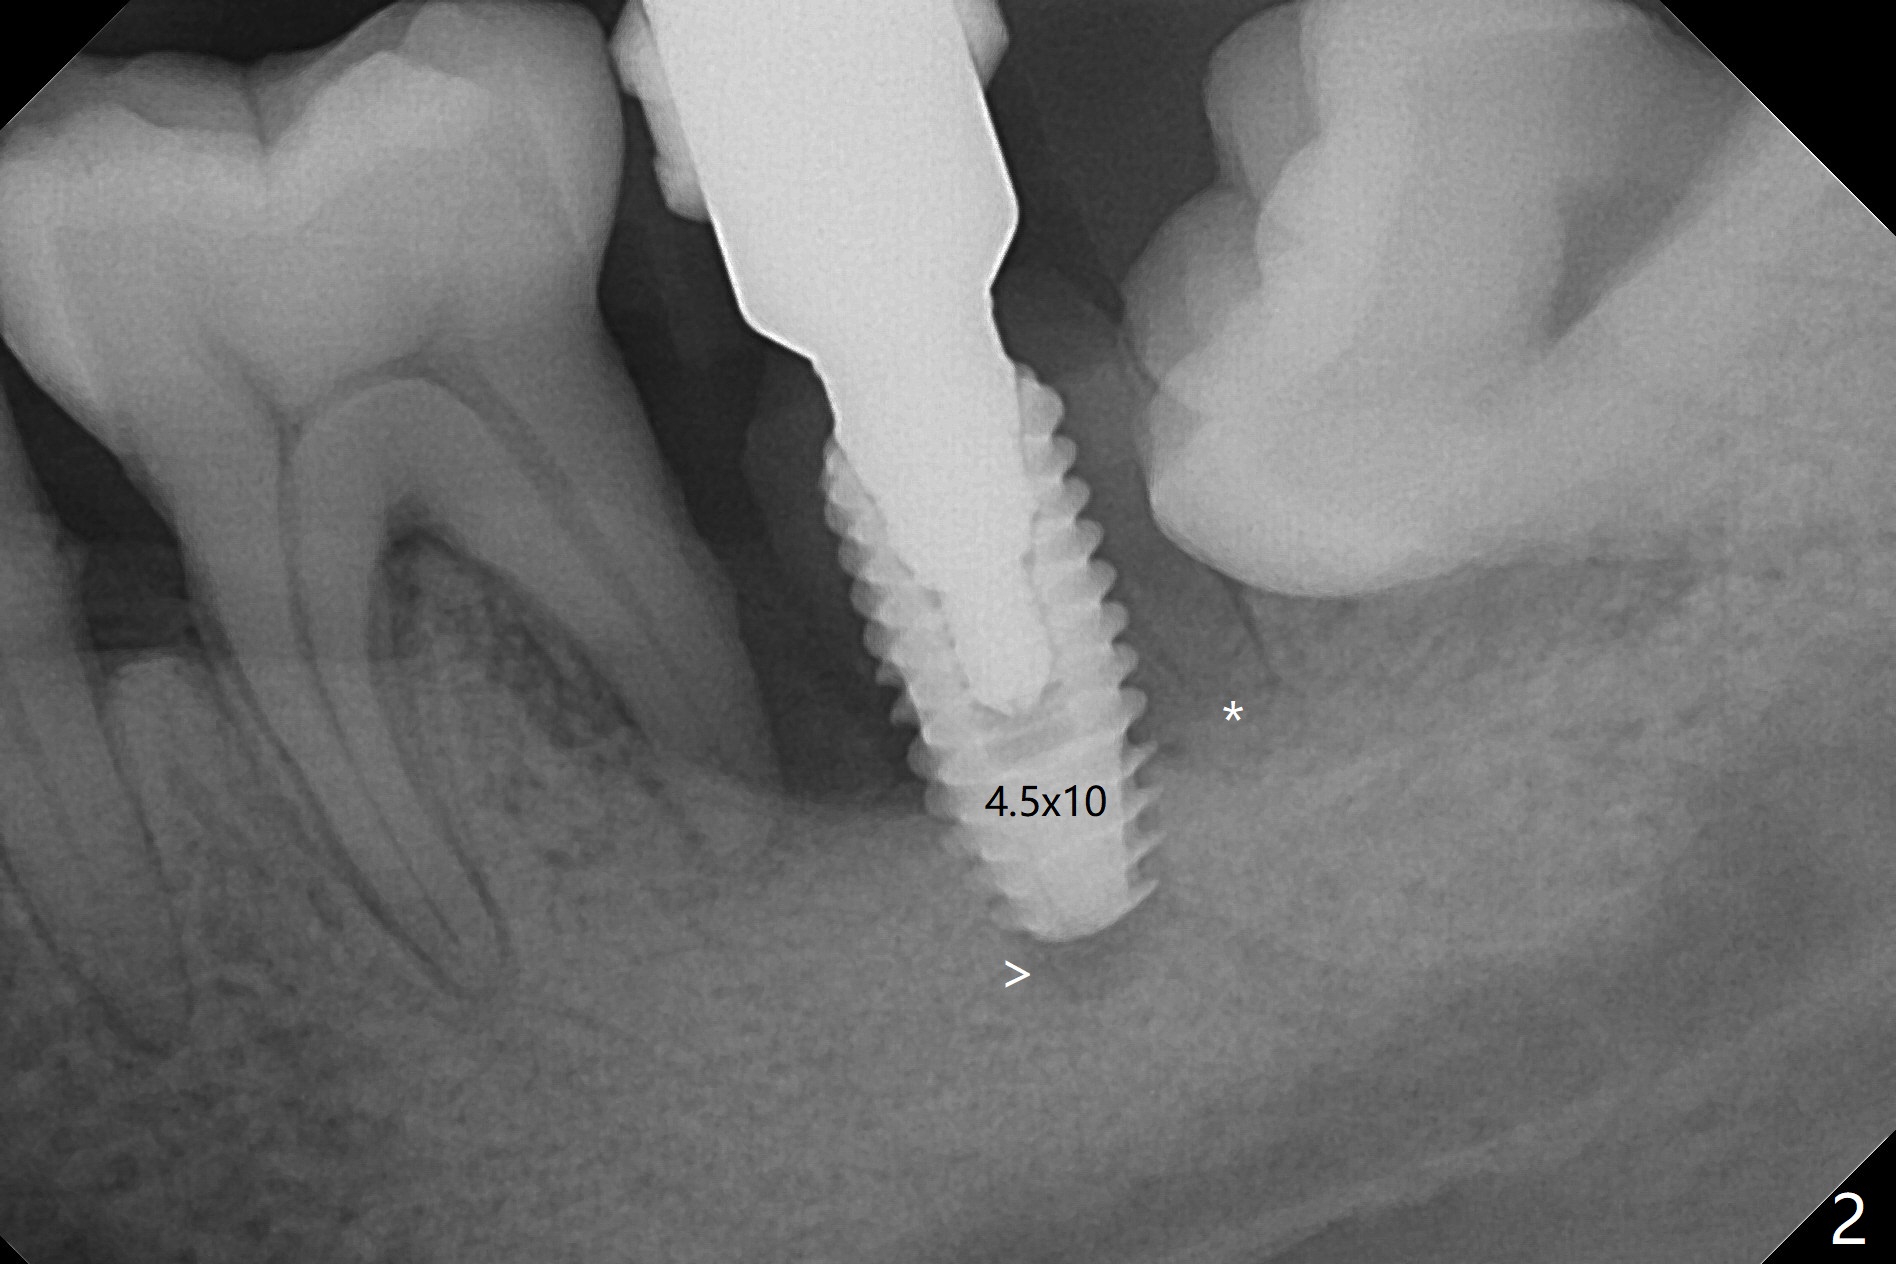

Socket shield (partial extraction therapies) is going to be conducted in this case to form a substitute buccal plate of the 2nd molar (Fig.1 *). The apex of the shield that contacts the 4.5x10 mm dummy implant cannot be removed because of poor access (Fig.2 * (12 mm offset)). Due to high bone density, a 4.5 mm drill has to be used in order to place a 5x7.3 mm definitive implant (Fig.3). In spite of the fact that the implant seems to be completely seated, the implant is ~ 1 mm supracrestal lingually. After implant removal, a 4.5x11.5 mm drill cannot reach the depth due to high bone density. 800 RPM instead of 50 RPM may help. When the implant is reseated, it appears to be .5 mm deeper than before clinically, although it looks incompletely seated in X-ray (Fig.4 <). The insertion torque is 60 Ncm. Allograft mixed with PRF is placed around the implant with cover screw, particularly mesiolinguodistal (Fig.4 *). The sockets of #17 and 18 are approximated with the help of 2 piece of PRF and collagen plug. The wound dehisces 9 days postop (Fig.5,6), although asymptomatic. Forced closure of the sockets with suture seems unnatural. An immediate provisional should have been fabricated. CT shows possible loss of part of bone graft (Fig.7). Regraft seems necessary in the appointment of uncover. Antibiotic is prescribed for another week. The gingiva seems healthy around the exposed healing screw 16 days postop (Fig.8). After debridement, the healing screw is then changed to a 4.5x5 mm healing abutment. The majority of the bone graft is lost without immediate provisional in 4 months (Fig.9 * (<: socket shield)). Then a 5.5x5 mm healing abutment is inserted for impression next appointment. A 5.2x4.5(4) mm cemented abutment is placed before impression (Fig.10). With socket shield (Fig.11 ^), the buccal gingiva looks more keratinized than the lingual one (Fig.12 *). Photos are taken immediately pre-cementation. Socket shield (*) covers the implant and abutment buccally (Fig.13 CT taken immediately pre-cementation).